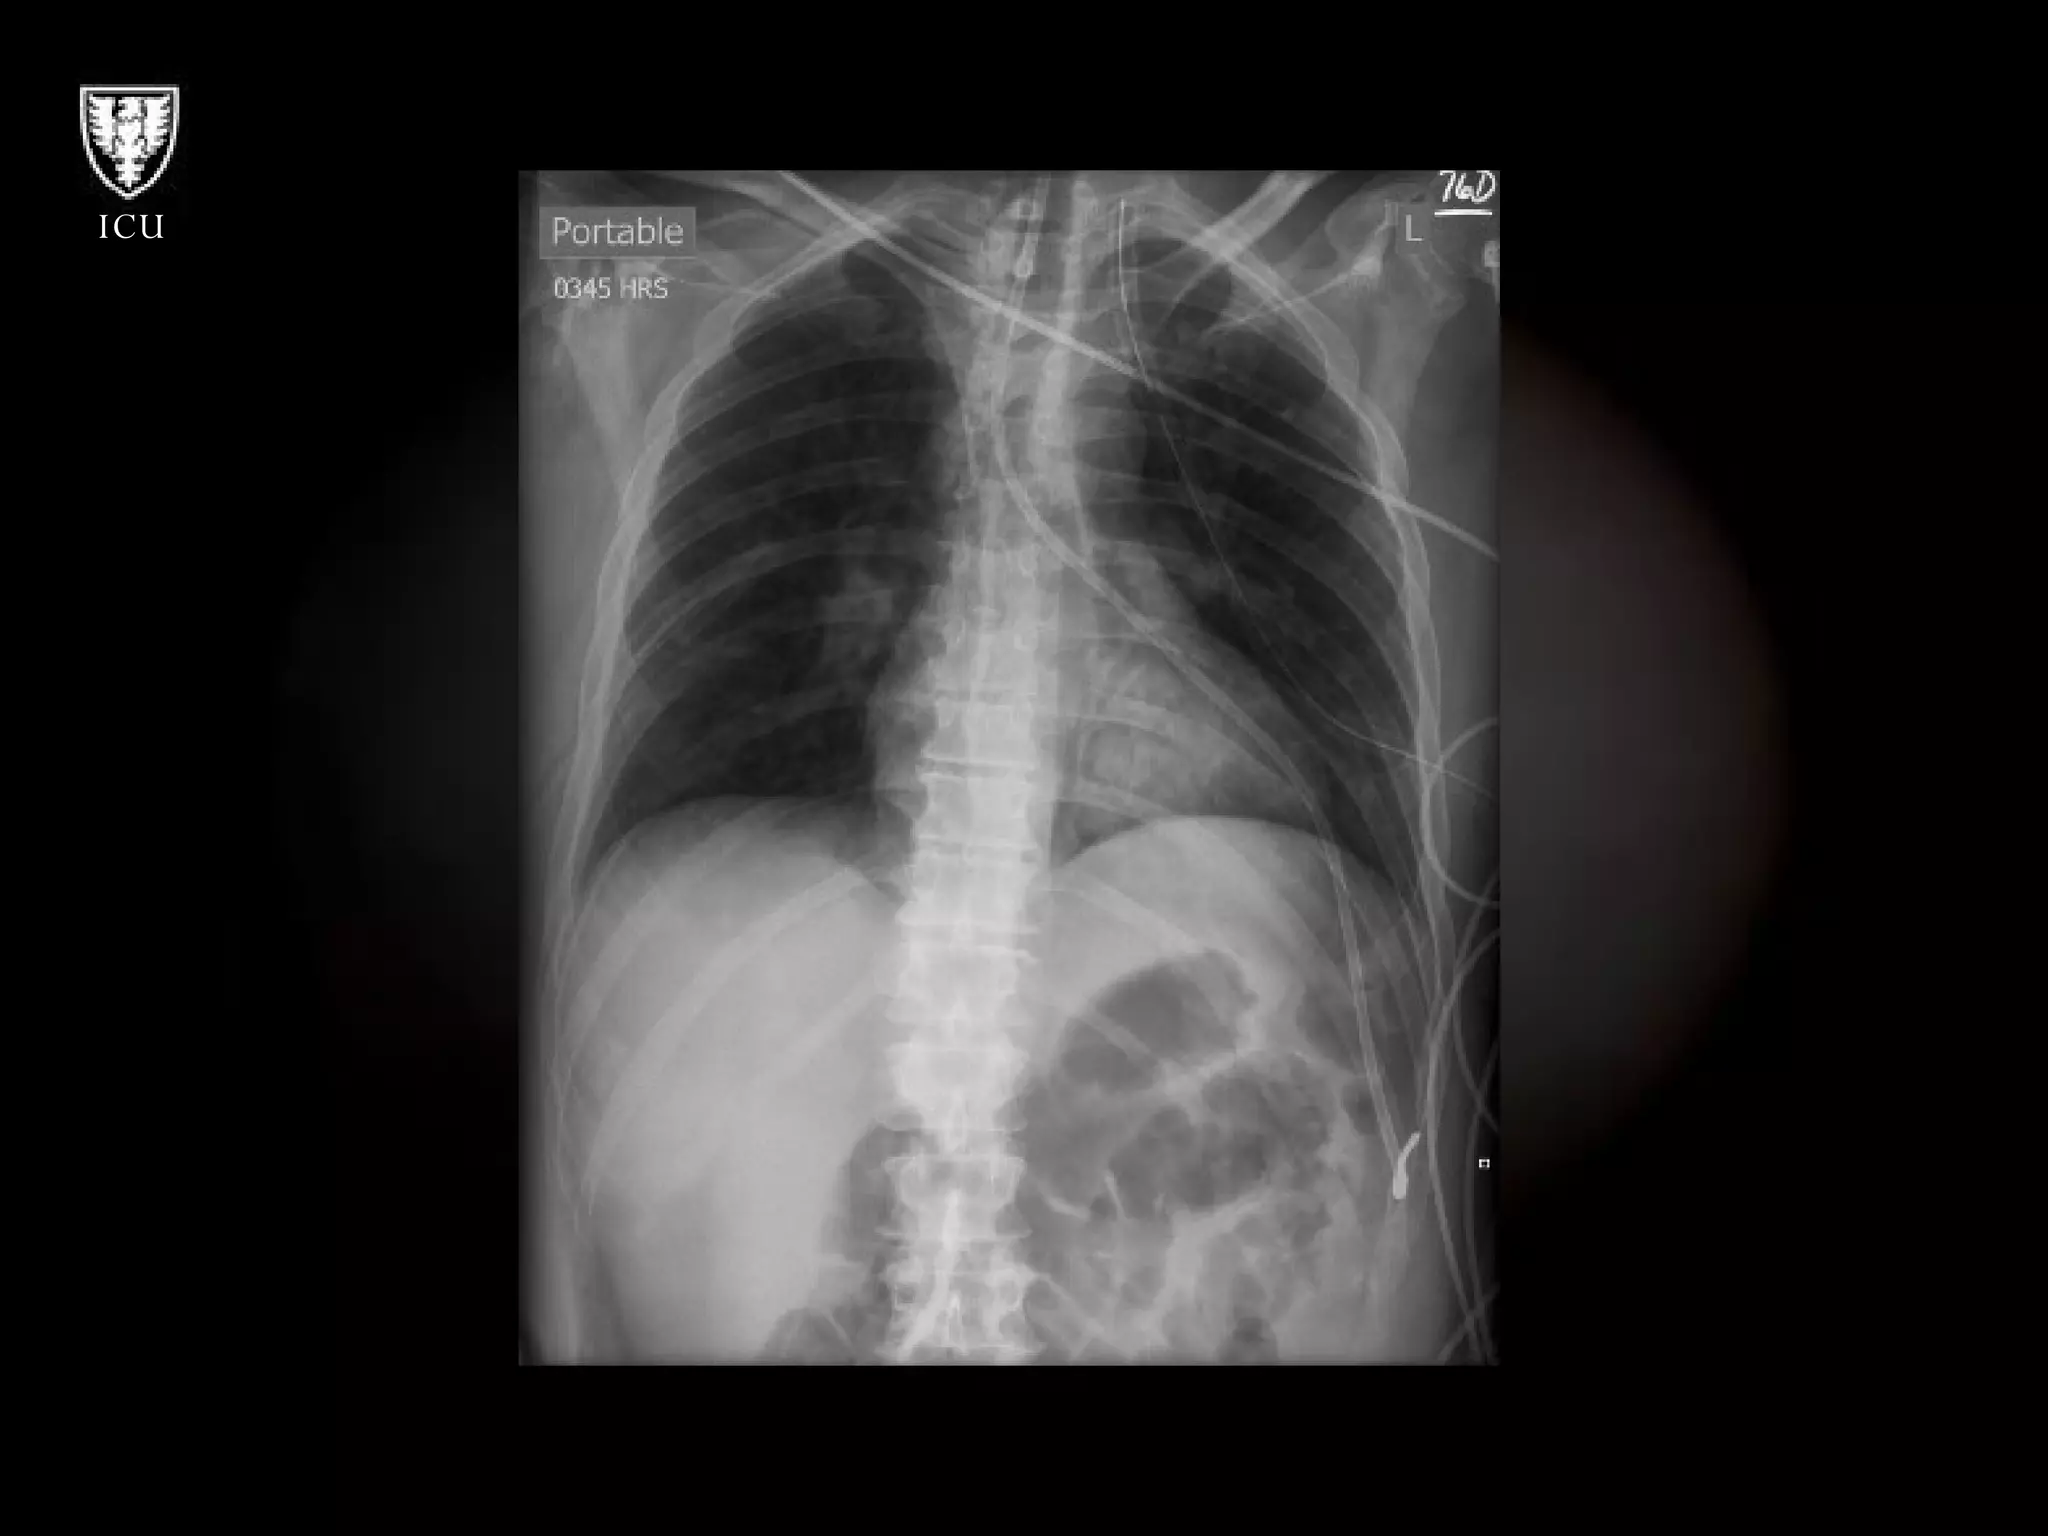

What’s Wrong With These Pictures?

What’s Wrong WithThese Pictures?